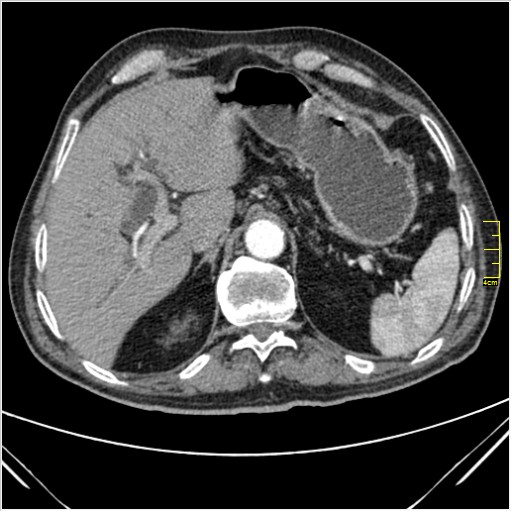

Мужчина 62 года с желтухой

Опухоль головки поджелудочной железы, расширение холедоха и панкреат. протока (Double Channel sign)

Карциномы панкреас гиподенсны на КТ с болюсом, т.к. содержать много соединительной и фиброзной ткани, в отличие от нормальной ткани железы, которая (как любая железа) хорошо васкуляризирована. Поэтому если видим в панкреас солидное гиподенсное образование - всегда настораживает на предмет рака. Второй момент: обязательная оценка взаимоотношения опухоли к ВБА и ВБВ, на предмет оценки операбельности.